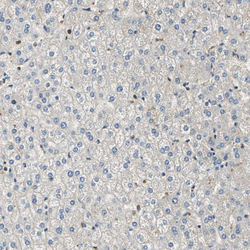

- Immunohistochemical staining of human liver shows weak cytoplasmic positivity in hepatocytes.

- Sample type

- HUMAN